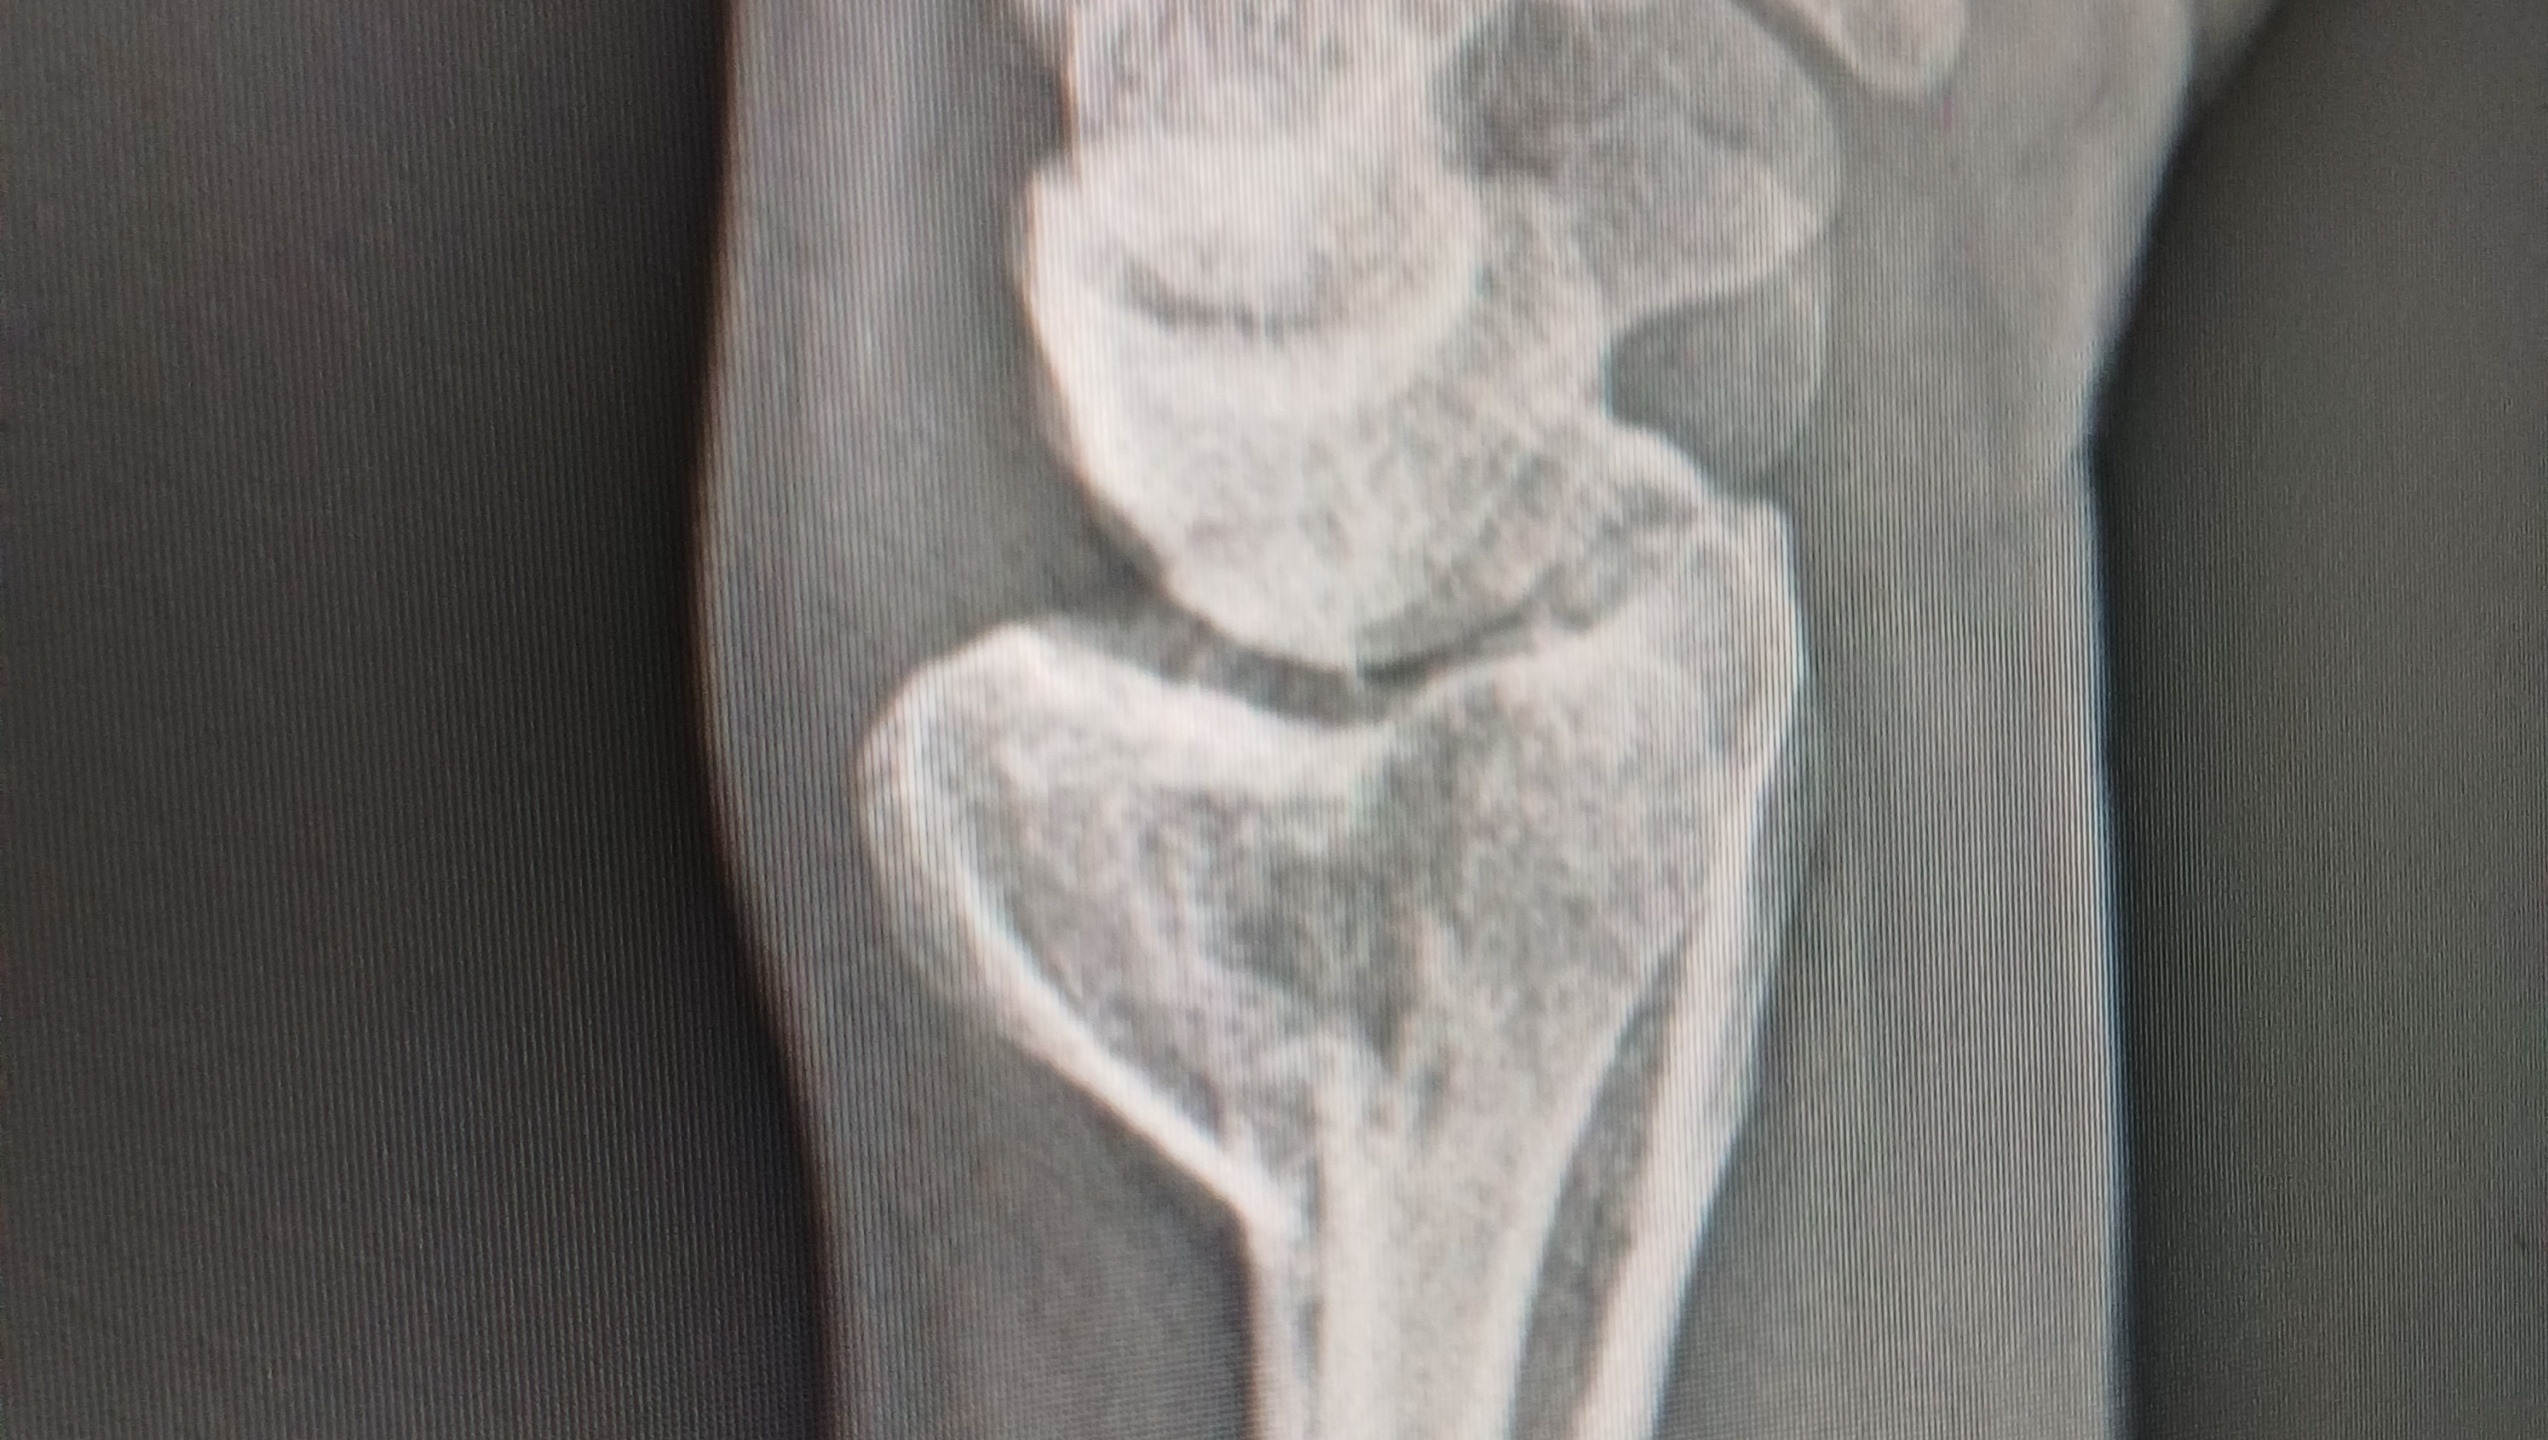

I have a Distal Radius Fracture... and it got fractured in many pieces and the pieces displaced. I'm currently dealing with pain but managing.

After consulting with the specialist, its been determined i will need surgery, which involves getting the wrist open and a metal plaque installed